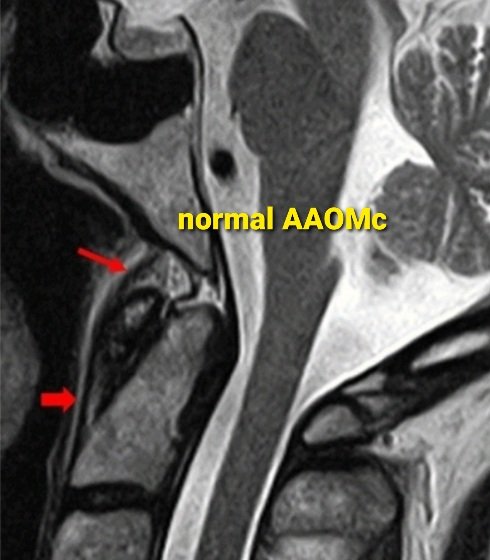

🔷90% of Anterior altlanto occipital membrane tears present with prevertebral effusion 🔷Prevertebral efffusion in screening CT in high velocity trauma patient➡️ Recommend cervical spine MRI @vebinars_neuro #NeuroRad #spinerad #radres #foamrad #Neurosurgery #spinesurgery

🤷‍♂️ Why care about Anterior Atlanto-Occipital Membrane (AAOM) tears? ✅ Routinely visible on #MRI ✅ Tears in 3️⃣ distinct patterns ✅ Presents w/ CCJ prevertebral effusion on #CT & major CCJ lig. injuries on #MRI ➡️ rdcu.be/dawhs #NeuroRad #NeuroSurgery #Spine

PeteFiesterMD's tweet image. 🤷‍♂️ Why care about Anterior Atlanto-Occipital Membrane (AAOM) tears?

✅  Routinely visible on #MRI

✅  Tears in 3️⃣ distinct patterns

✅  Presents w/ CCJ prevertebral effusion on #CT & major CCJ lig. injuries on #MRI

➡️ rdcu.be/dawhs

#NeuroRad #NeuroSurgery #Spine